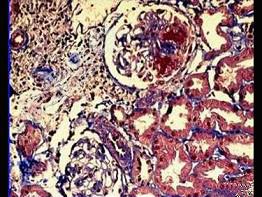

- 单项选择题阅读下述三张狼疮性肾炎病理图片后,其病理诊断为 ( )

A、Ⅲ型LN

B、Ⅰ型LN

C、Ⅳ型LN

D、微小病变病

E、Ⅱ型LN